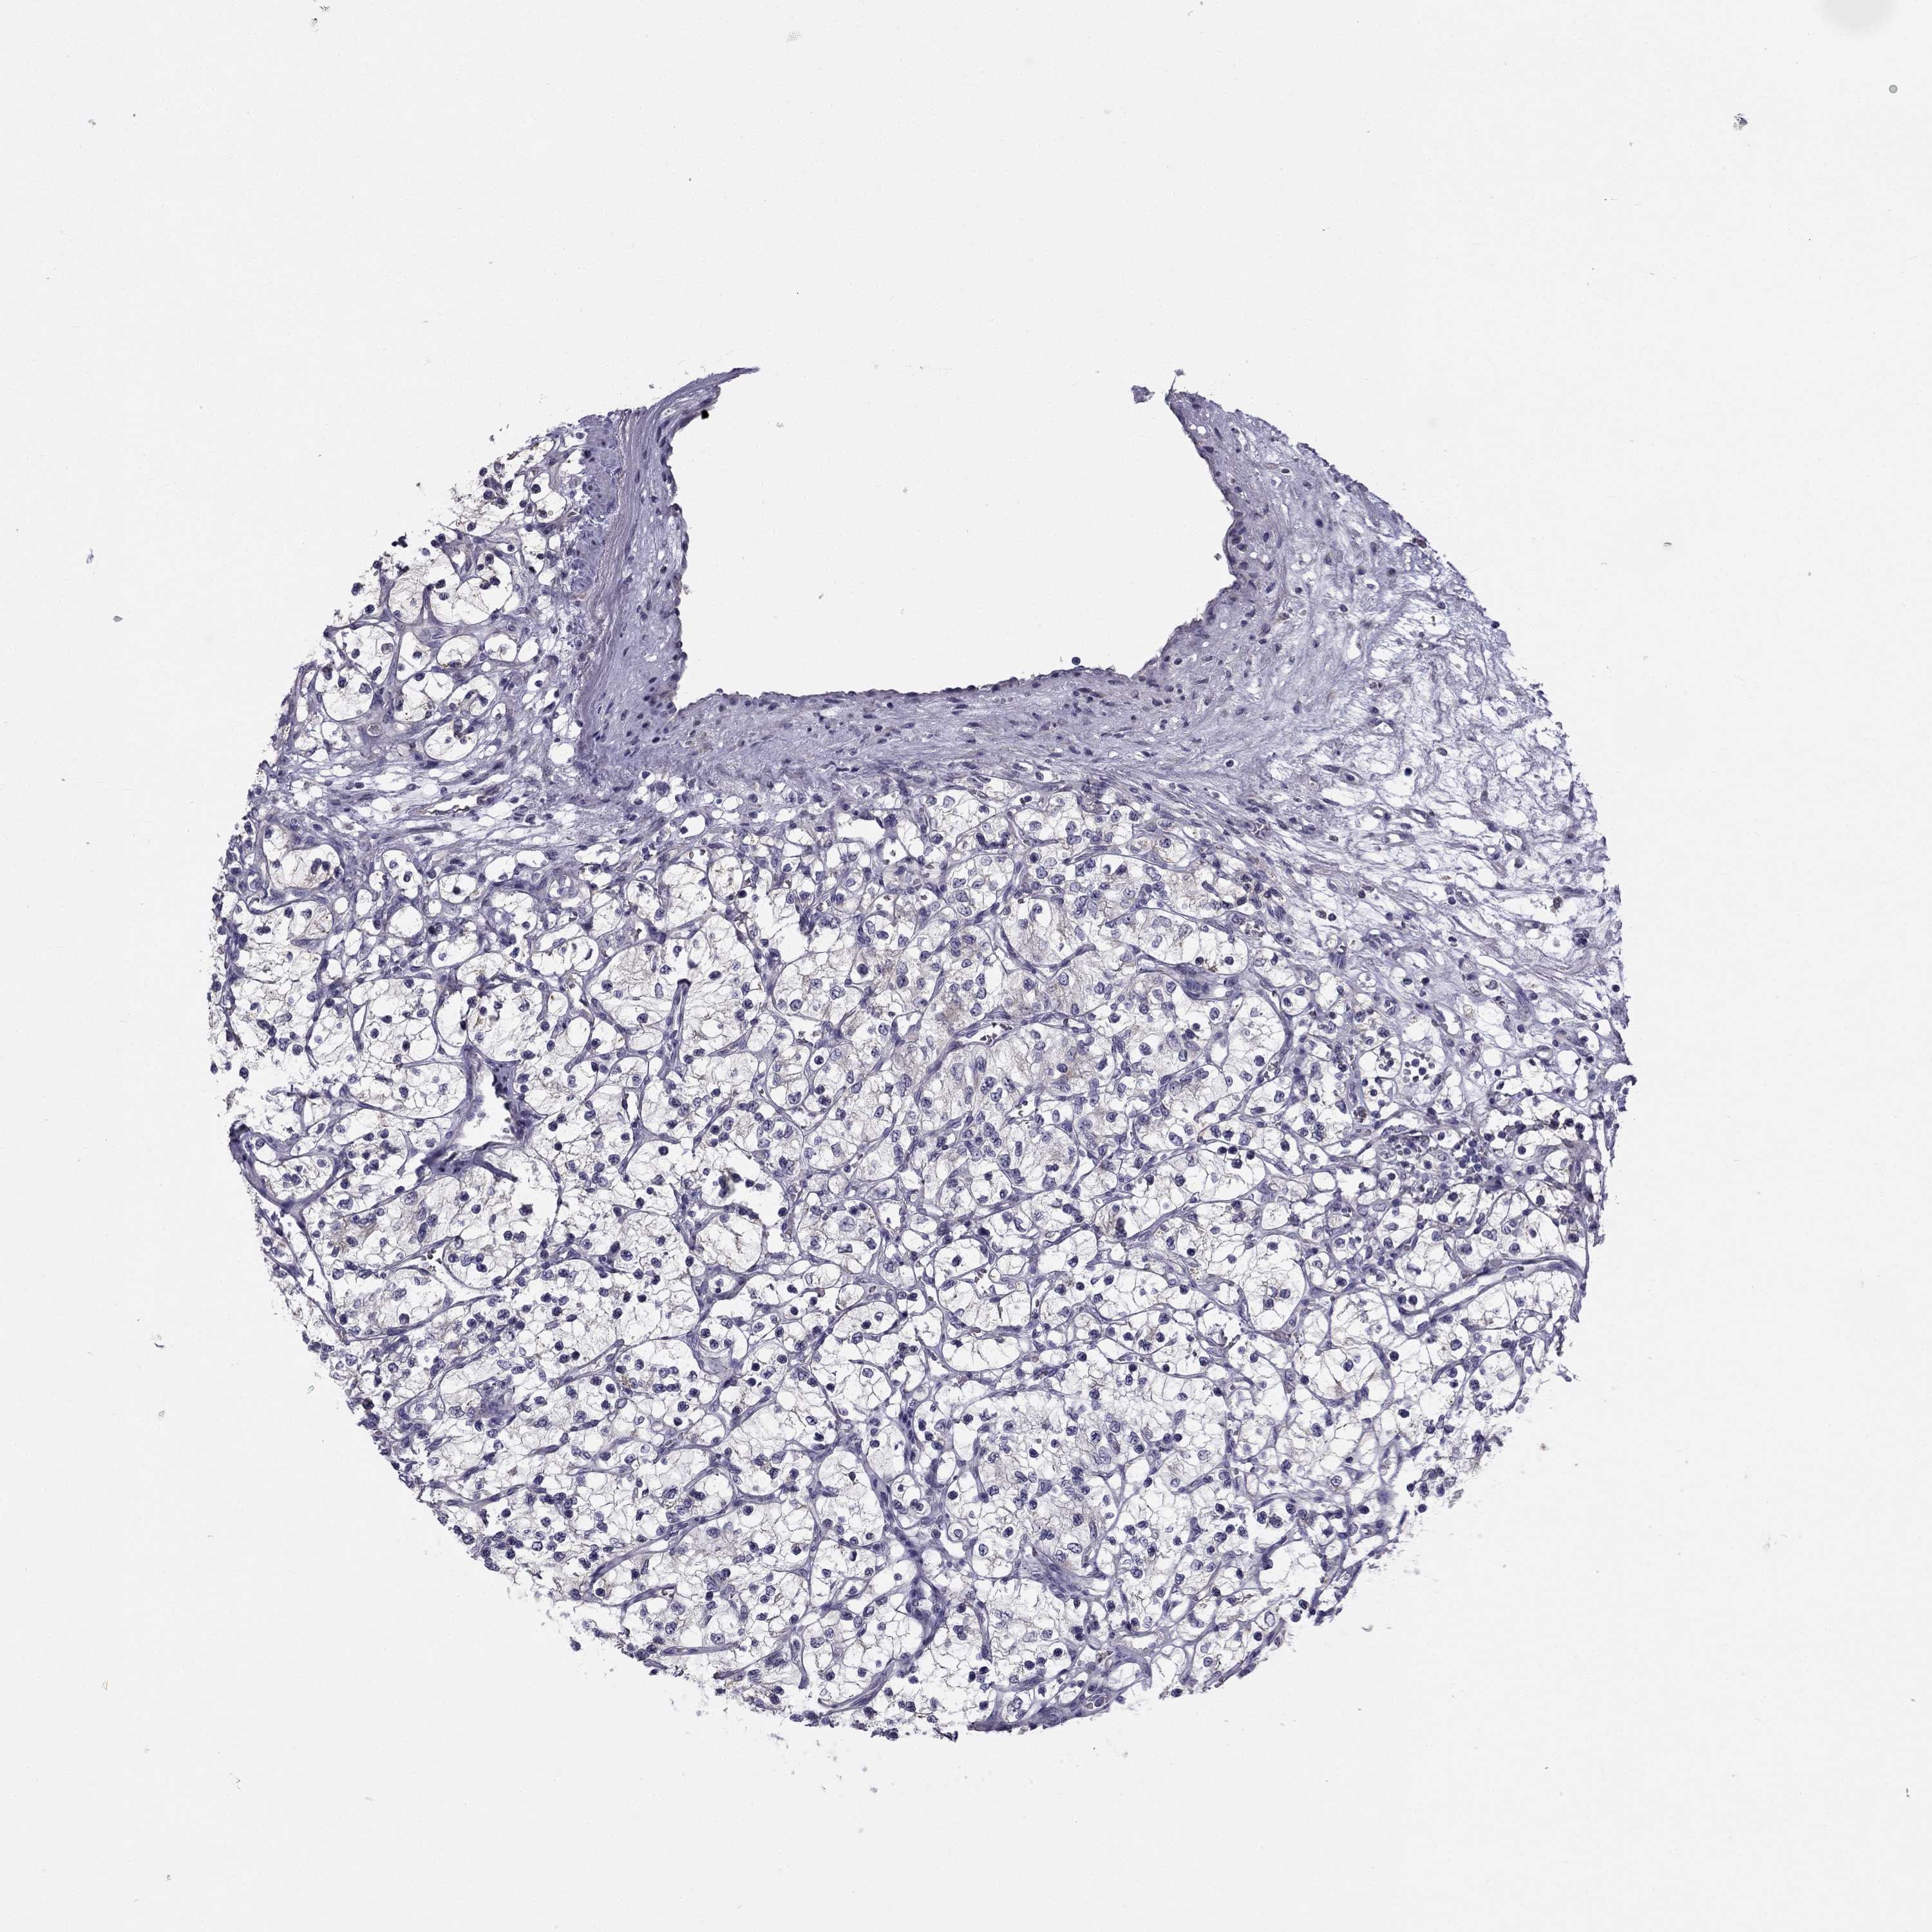

CANCER RENAL CANCER Show tissue menu

KICH TCGA KIRC TCGA KIRC VALIDATION KIRP TCGA PROTEIN RCC CPTAC PROTEIN EXPRESSION

ANTIBODIES

AND

VALIDATION